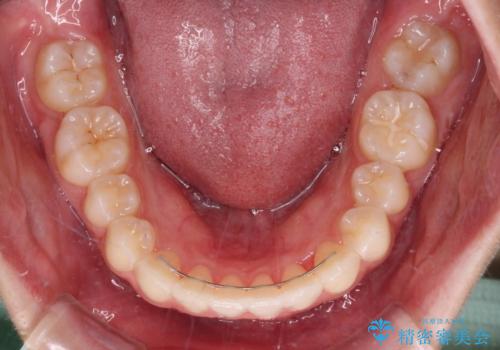

- 1年9ヶ月

インビザライン特有の、奥歯の咬み合わせの問題もなく、しっかりと歯列を改善することができました。

舌側転位している上顎側切歯(内側に引っ込んでいる真ん中から2番目の歯)は、インビザラインが最も移動を苦手とする歯であり、これ以上の改善を望まれる場合にはワイヤー矯正、あるいはワイヤー矯正の併用をお勧めいたします。